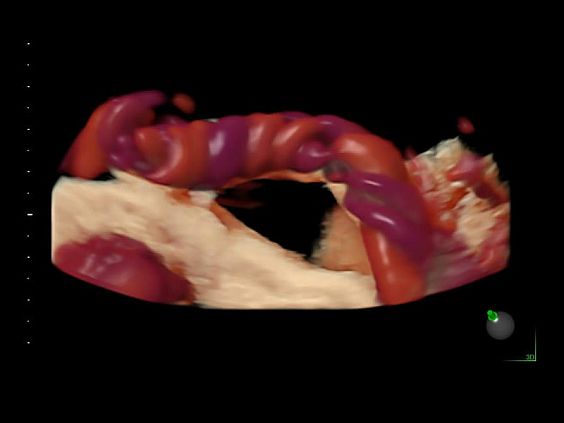

• Высокочувствительный допплер (HD-Flow)

• Реалистичный объёмный кровоток в режиме ЦДК (Radiantflow)

• HDlive Flow - перемещаемый источник света, совместимый с визуализацией кровотока в 3D

• HDlive Flow Silhouette - режим "Силуэт" с выделением границ полостей сердца и сосудов, совместимый с визуализацией кровотока

• Advanced STIC - расширенный программный пакет для исследования сердца плода в режиме 4D для механических и электронных объемных датчиков:

• Использование цветного, энергетического допплера, В Flow - режим STIC.

• Перемещаемый источник света - STICflow

• SonoVCADHeart - программное обеспечение для исследования сердца плода в режиме 3D/4D (быстрый доступ к плоскостям сканирования) по рекомендациям ISUOG

• Технология HDlive Flow — повышает реалистичность визуализации сосудистых структур, улучшая восприятие глубины (по сравнению с традиционным цветовым допплером и функцией HD-Flow).